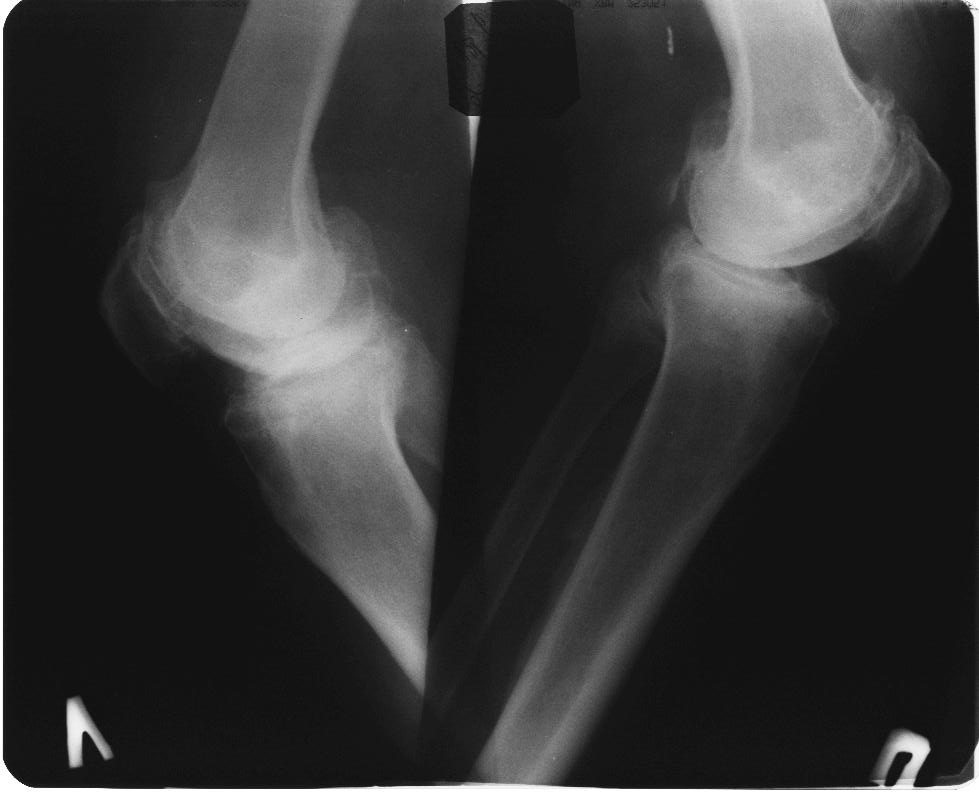

вообще, то в комплекс симптопатической терапии входят всякие медикаменты + ИСЖ (гиалуронаты) + гормоны при "мокром" суставе + физиолечение + грязи + солнце - воздух и вода + доброе слово и участие доктора и все это.... не удел ортопеда -хирурга. Это ближе к терапии. Чуть агрессивнее различные артроскопические санации и манипуляции - временно помогает + ИСЖ + фиксаторы + ортезы + аппараты + трость и костыли + коляска. Однако судя по рентгенограммам - суставы приговорены к эндопротезированию.

Глядя на снимки, кроме оперативного лечения в голову ничего не приходит. Хотя бы корригирующая кортикотомия б/б кости с минимальной внешней фиксацией. Высылаю пример.

Откровенно говоря, прочитав ваше суждение по теме о возможности неоперативного лечения двустороннего гонартроза, варусной деформации,сильно

Каждому методу свое время и место. у обсуждаемого пациента очевидна перегрузка медиальных отделов суставов с разрушенными суставными поверхностями, каким образом, вы представляете себе облегчить боли НПВП (разнообразие которых столь велико, что больному не хватит жизни и здоровья, чтобы все перепробовать, но идля *участливого* доктора всегда есть путь к отступлению - не помогает один, давайте попробуем другой - бесконечный,

Я всячески поддерживаю тактику оперативного вмешательства. Но просто тема консервативного лечения, надеюсь Вы согласитесь, на форуме обсуждается КРАЙНЕ РЕДКО И НЕОХОТНО. А применительно к выложенным R-граммам, конечно, показано Эндопротезирование, но только заголовок обращения сразу расставляет приоритеты в пользу консервативных методик. Причины тому могут быть самые разнообразные, нам о них не сообщили. Так зачем же предлагать коллегам то, чего они делать не будут?